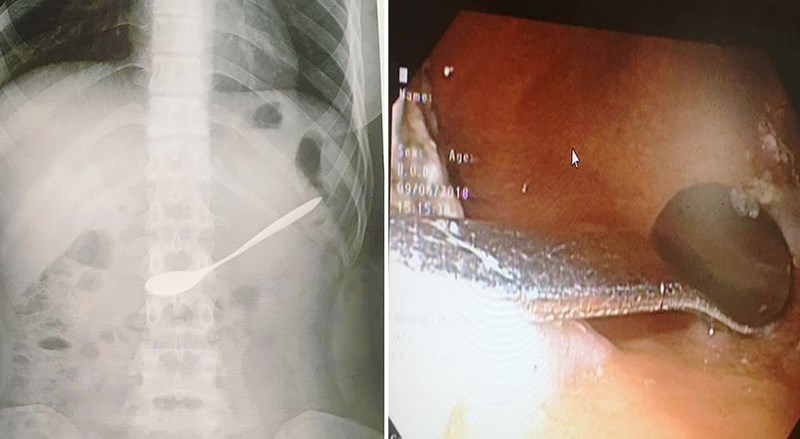

Hình ảnh chiếc thìa nằm trong ổ bụng của bệnh nhân.

Ngày 10/6, thông tin từ Bệnh viện Đa khoa TP. Vinh (Nghệ An) cho biết, bệnh viện vừa tiếp nhận và gắp một chiếc thìa ra khỏi bụng một nữ bệnh nhân 20 tuổi.

Trước đó, vào khoảng 12h trưa 9/6, chị L.T.N.A (20 tuổi, trú huyện Hưng Nguyên, Nghệ An) ngồi uống cà phê với bạn.

Trong lúc uống, chị A. không may bị bạn thúc vào tay nên đã vô tình đã nuốt chiếc thìa bằng kim loại vào họng. Do mắc vào họng, chị A. và bạn không lấy được ra nên thìa trôi vào bụng.

Ngay sau đó, chị A. được người bạn đi cùng đưa tới Bệnh viện Đa khoa TP. Vinh để cấp cứu.

Ngay khi tiếp nhận nữ bệnh nhân, qua kiểm tra và thăm khám, các bác sĩ phát hiện chiếc thìa nằm tại hang vị dạ dày. Sau đó đã tiến hành gắp dị vật này ra khỏi người bệnh nhân.

Hiện, sức khỏe của chị A. đã hồi phục và xuất viện về nhà.